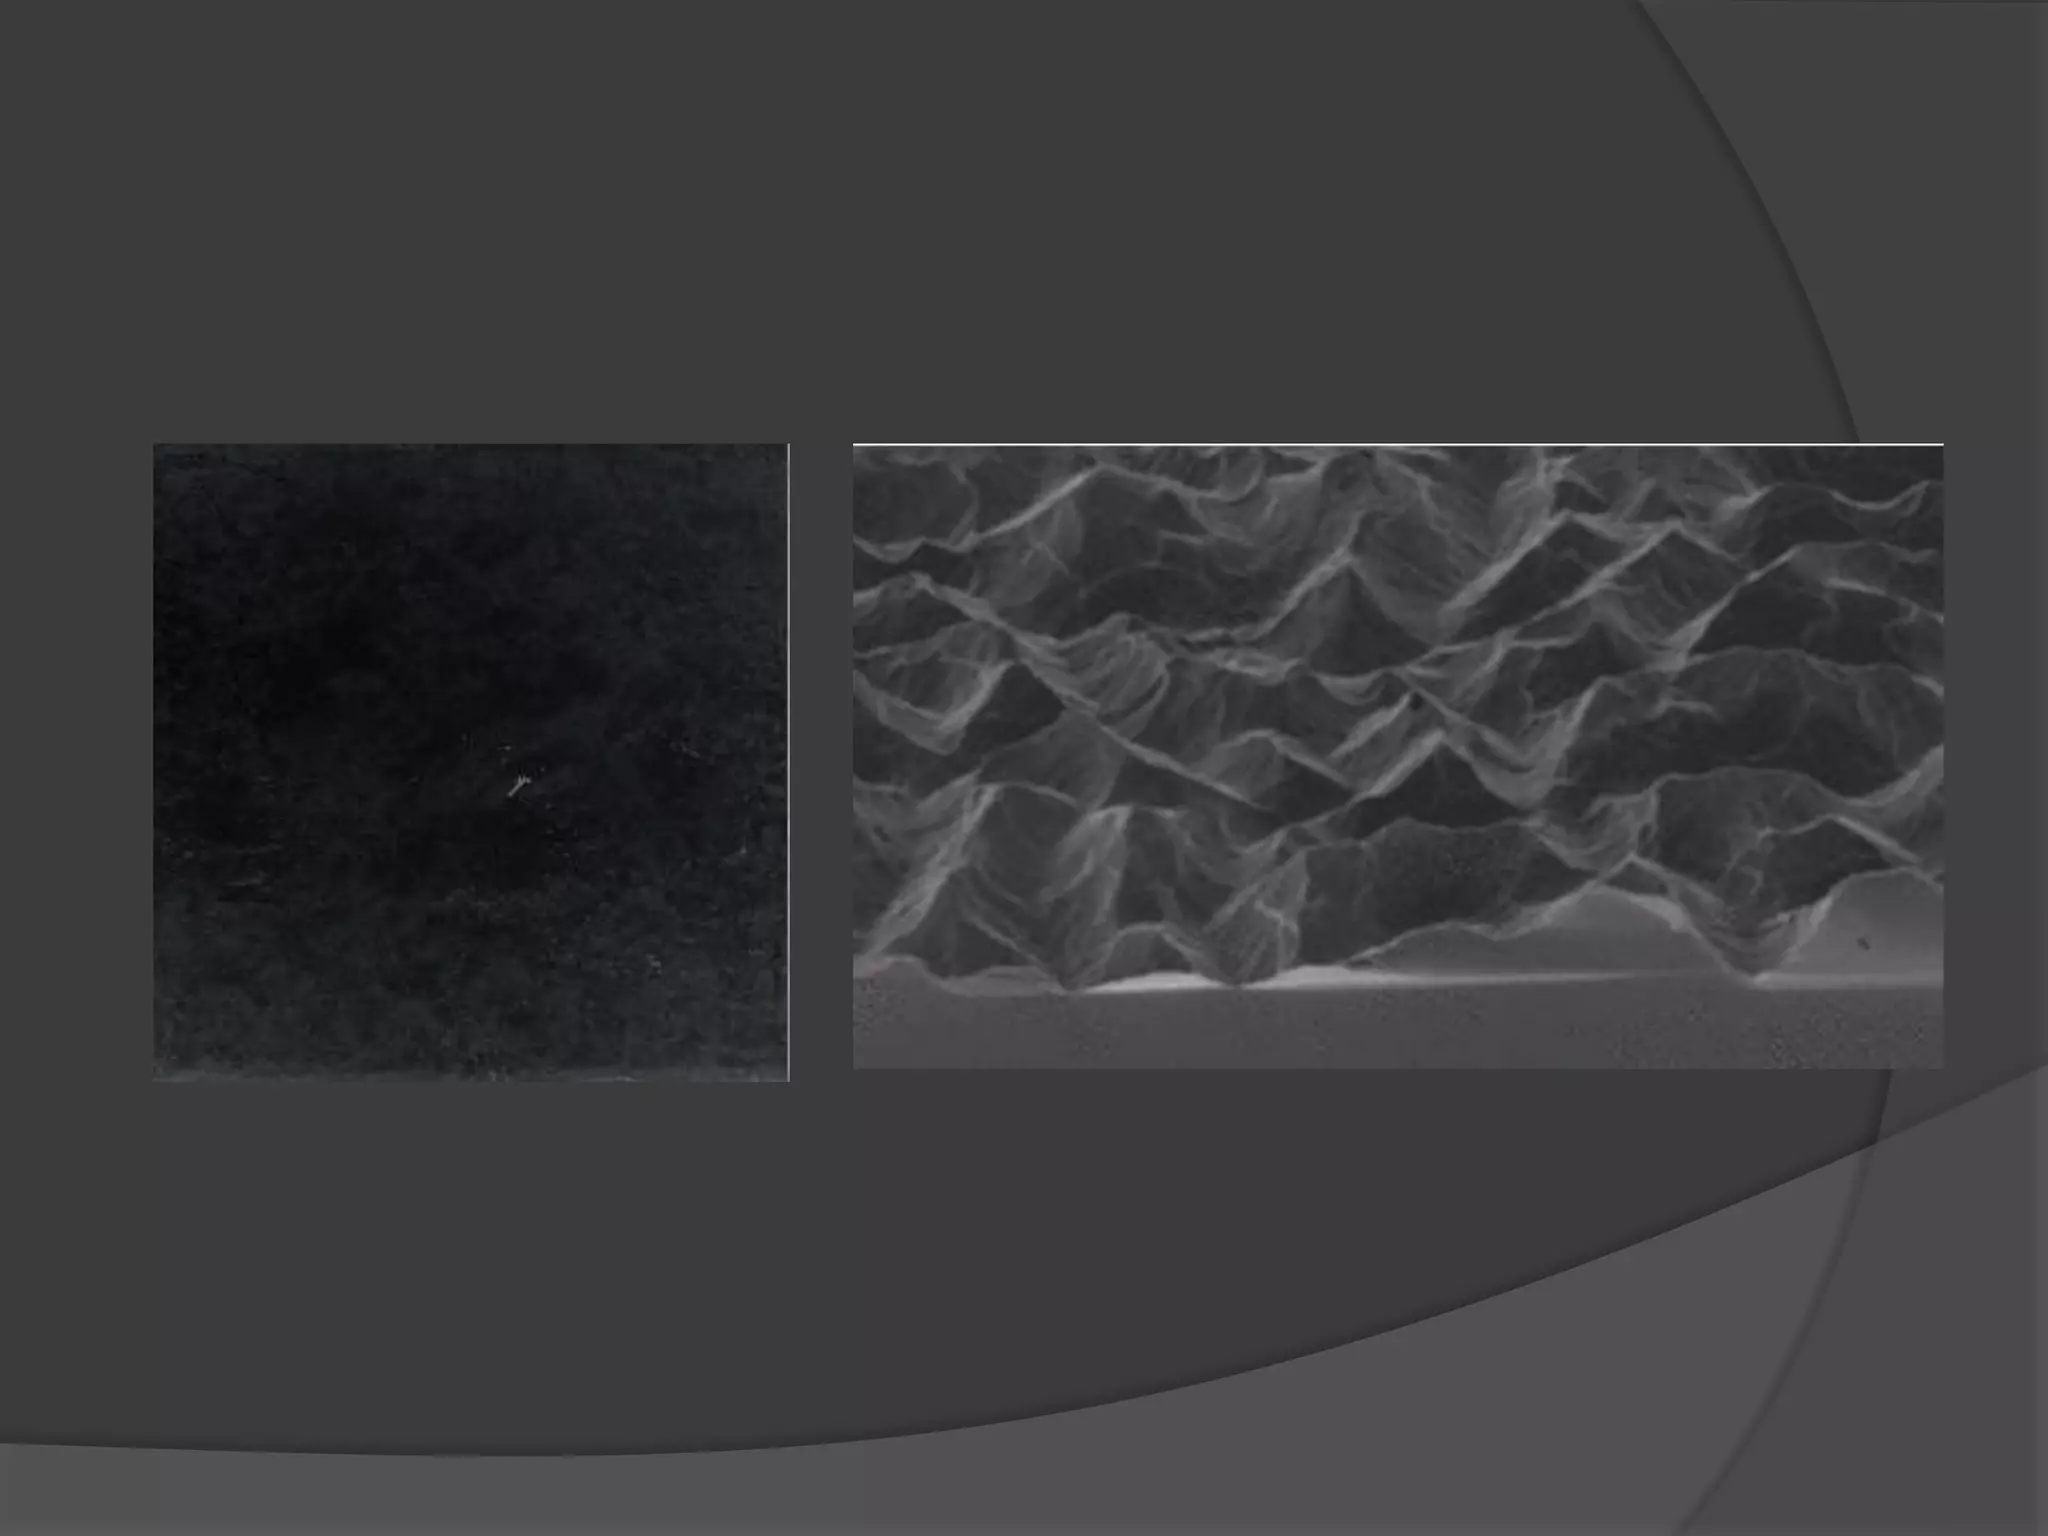

This document discusses factors that influence osseointegration and primary stability of dental implants, including implant design characteristics, surgical technique, and loading protocols. Specifically, it covers the processes of osseointegration and how forces on implants can either promote or inhibit bone remodeling. Key implant design considerations like length, diameter, threads, coatings and surface topography are analyzed in terms of their effects on stress distribution and bone-implant contact. The importance of primary stability and factors influencing it like bone quality and surgical skill are also addressed. Loading protocols ranging from immediate to conventional loading are compared.